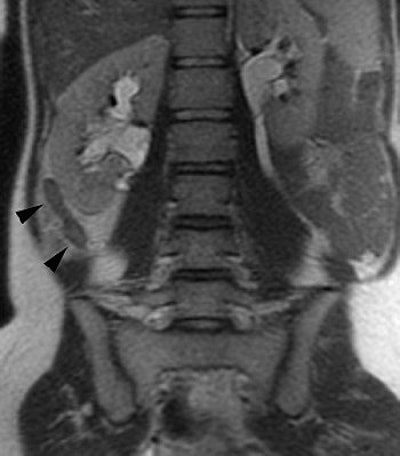

| Coronal single-shot fast spin-echo (SSFSE) image in pregnant patient with RLQ pain shows an enlarged blind-ending tubular structure (arrowheads) adjacent to the right kidney. Image courtesy of Dr. Ivan Pedrosa. |